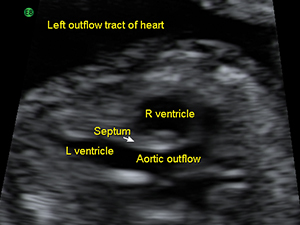

Heart